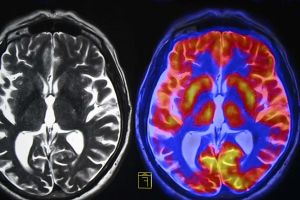

A CT scan or an MRI of your head can reveal stroke symptoms. Blood clot symptoms can be ruled out with tests of your heart and blood arteries in your neck.